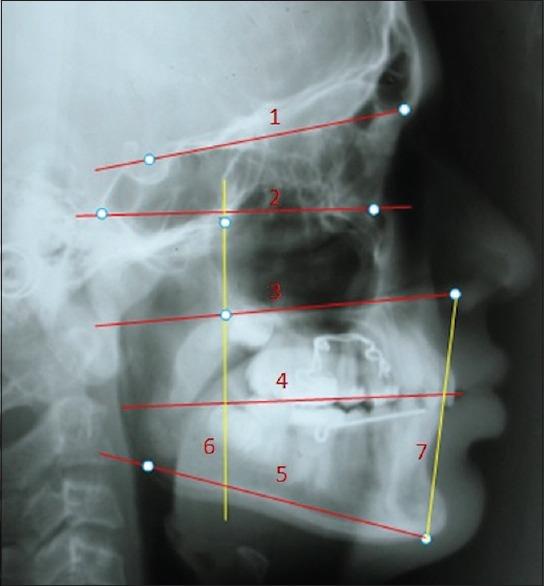

Pretreatment and postdistalization lateral cephalograms and study models of 20 subjects (6 males, 14 females) Class II malocclusion subjects were examined. PA and JJ group both consisted of 10 patients each with a mean pretreatment age of 12 years 1 month for females and 12 years 5 months for males. The PA and the JJ appliance were activated once in a month until Class II molar relationship was corrected to a super Class I molar relationship in both groups. Initial and final measurements and treatment changes were compared by means of Paired -test.

Maxillary first molar distalized an average of 3.85 mm in the PA and 2.75 mm in the JJ between T1 and T2; rate of molar distalization was 1.59 mm/month for PA, and the JJ appliance averaged 0.88 mm/month, distal molar tipping was greater in PA (6.2°) than in the JJ (3.9°). Average mesial movement of the premolars was 2.2 mm with PA and JJ both. JJ showed a greater rotation of first molars after distalization as compared to PA. The increase in vertical facial height was also greater for JJ as compared to PA.